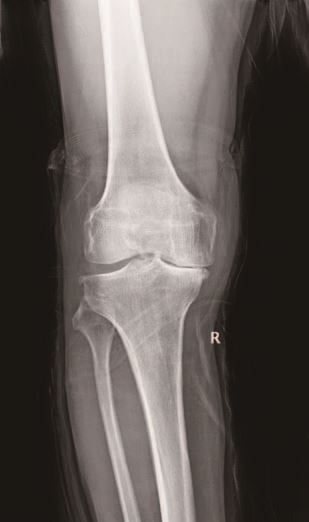

67岁的王大爷三年前出现右膝关节疼痛,经过多次口服药物、理疗等保守治疗,效果越来越不好,如今行走200-300米左右就疼痛难忍,严重影响日常生活,于是在家属的陪同下来到我院就诊。经X光片检查显示,王大爷术前膝关节活动度伸直5°,屈曲120°,轻度内翻畸形,被确诊为右膝骨性关节炎,医生建议手术治疗。5月20日,医生们为其实施了人工膝关节单髁置换手术,手术进行顺利,术后王大爷的手术切口愈合较好,膝关节内翻畸形纠正,1周内经过锻炼膝关节伸直5°,屈曲110°,王大爷对手术及术后功能恢复非常满意。